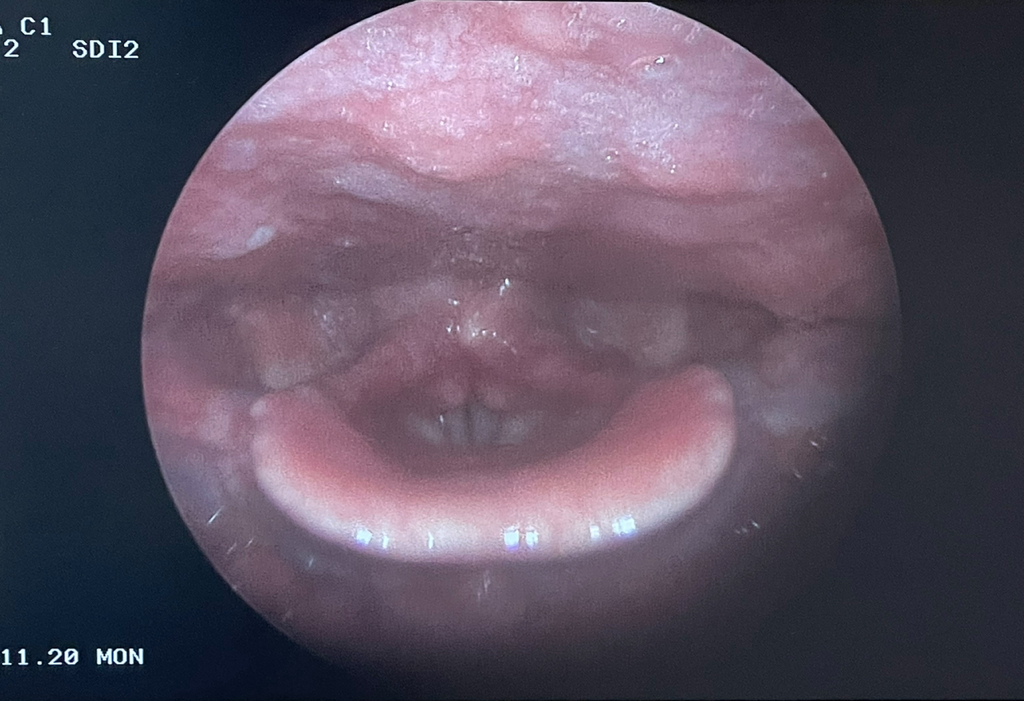

(사진있음) 인후염이 있다고 하는데 운동해도 되나요?

콧속도 빨갛고 부어있고 목쪽은 그냥 다 부어있다는 것 같았어요

• 1번 째 사진